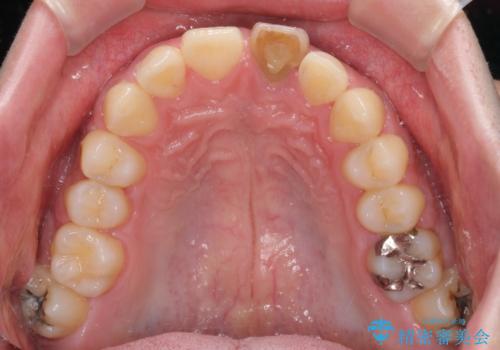

- 中学生の時にぶつけて以来、そのままにしていたところ前歯が変色してきたとのことで来院された患者様です。

レントゲン写真より、歯の中の神経組織が失活していることが分かったため、根管治療、ファイバーコアによる土台築製を行い、オーダーメイドタイプのオールセラミッククラウンにて補綴することとしました。